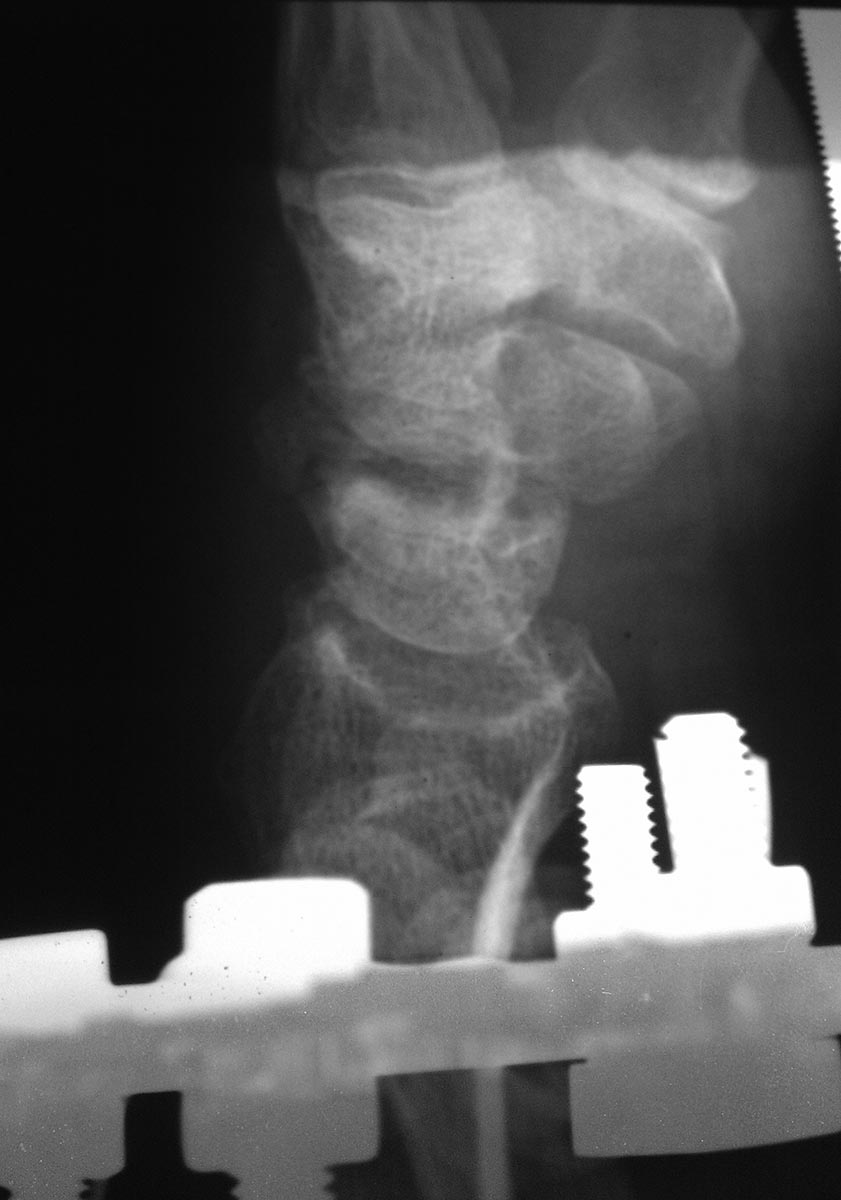

[Ortho] Перелом (ложный сустав?) ладьедидной кости правой кисти

Снимок от 18.03.16 после закрытой репозиции на аппарате Илизарова.